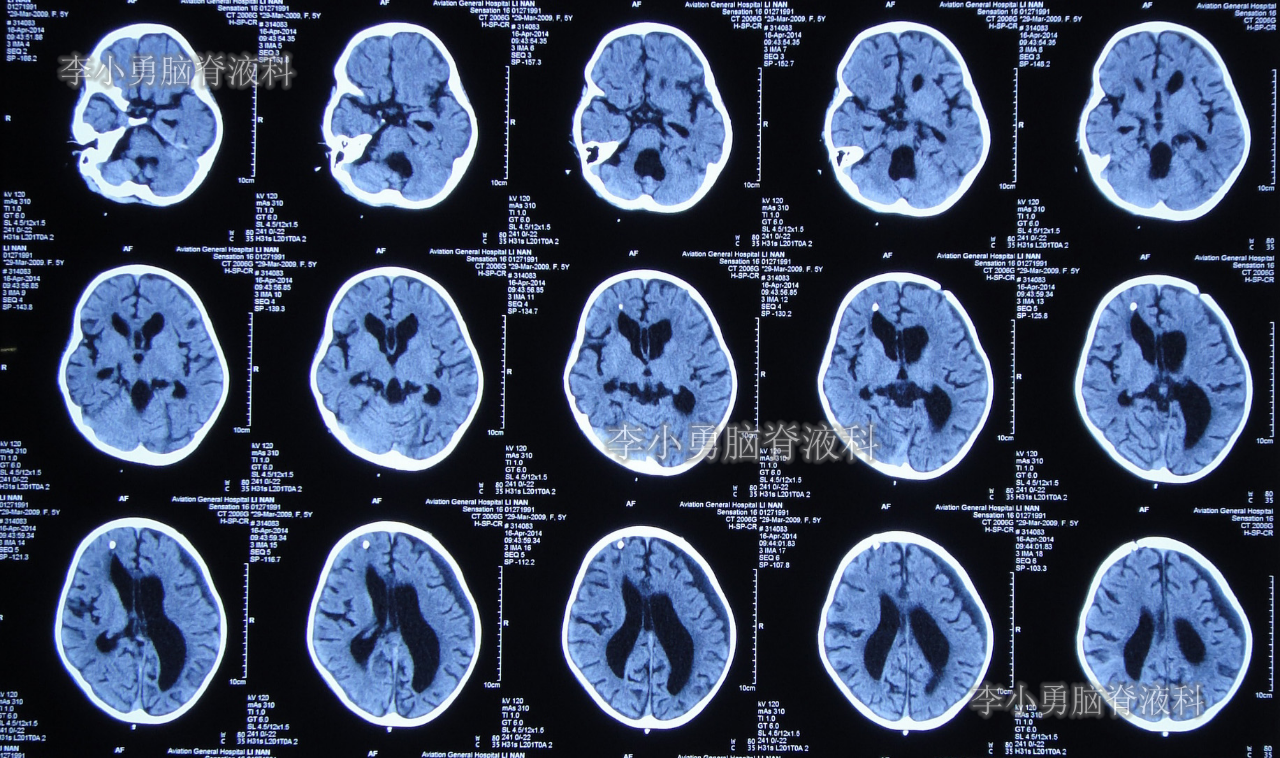

于2014年2月11日即脑室心房分流术后第122天时,患儿突然再次出现头痛和呕吐的症状,立即又第3次返回河南省郑州市某三甲医院神经外科住院治疗,当天查头颅CT显示脑室系统再度扩张严重(图-2)。

图-2:2014年2月11日头颅CT

第3次住院后第10天即2014年2月21日,复查头颅CT显示脑室系统仍扩张严重(图-3)。

图-3:2014年2月21日头颅CT